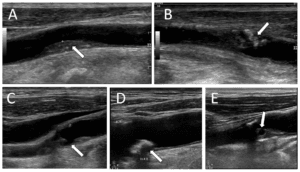

The final clinical application of ML for POCUS discussed here is deep-venous thrombosis (DVT) screening. POCUS is an important tool for physicians treating potential DVT patients within the emergency room as well as in the inpatient setting. POCUS can guide clinical decision-making for patients at risk for, or suspected of having, a pulmonary embolism [44]. During the exam, the deep veins of the lower extremity are compressed along their course and areas of low compressibility suggest potential thrombus formation at that location. Recently, Nafee et al. sought to evaluate the performance of two ML models they developed versus a validated DVT scoring system in acutely ill patients. Their study demonstrated that both of their ML apporaches outperformed the validated manual scoring system in predicting venous thromboembolism (VTE)  (c-statistic: ML methods = 0.69 and 0.68, manual scoring system = 0.59) [45].

Other models such as that by Tanno et al. have aimed to increase classification accuracy of DVT scans by automatically detecting the extent of vein compressibility in DVT scans [46]. Researchers proposed a dual-task CNN to predict vein compressibility with an F1 score of 90% when evaluated on 1150 5–10 s compression image sequences from 115 healthy volunteers resulting in a data set size of approximately 200k labelled images. As further development continues, these advancements may greatly increase the accessibility and clinical usage of this already impactful diagnostic study.